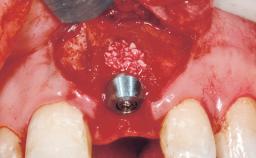

Late Flapless Placement of an Implant in a Maxillary Left Central Incisor Site

A 39-year-old male patient presented with a chief complaint of discomfort and gingival discoloration around his maxillary left central incisor. He was in good general health and was a non-smoker. His past dental history was significant because of the traumatic fracture of tooth 21 in a sporting accident at age 13. Initial dental treatment included endodontic therapy and a full-coverage restoration. The patient became symptomatic 5 years later, when structural failure of the tooth resulted in the dislodgment of the crown. Endodontic retreatment, apical surgery, and post-and-core restoration were performed.

Bone Augmentation Horizontal|Staged

Augmentation Materials Xenogenous|Membrane

Bone Volume Deficient horizontally, requiring prior grafting